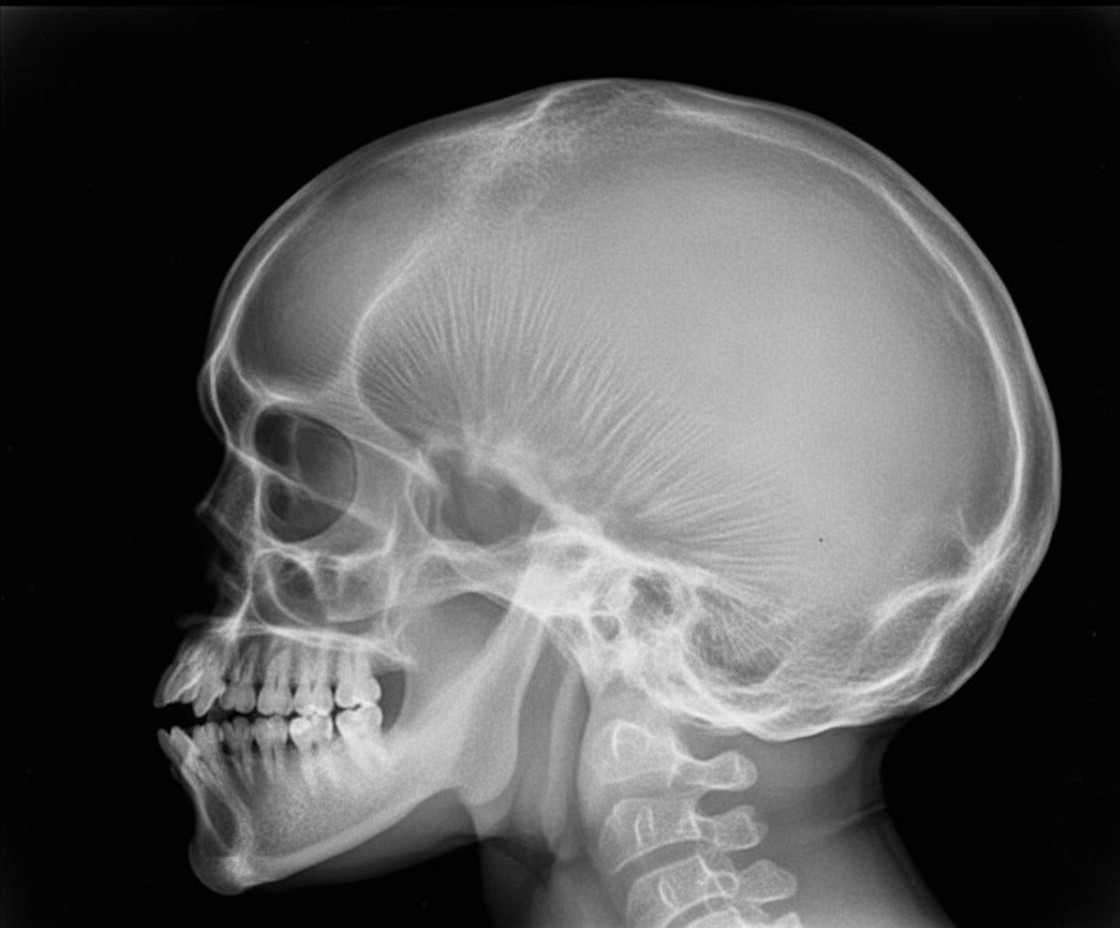

The following X-ray skull shows:

Explanation: ***Thalassemia*** - The X-ray shows changes consistent with **extramedullary hematopoiesis** in the skull, a classical finding in severe **thalassemia**. - This typically manifests as a **'hair-on-end' appearance** due to widening of the diploic space and thinning of the outer table of the skull from expanded bone marrow. - This is most commonly seen in **beta-thalassemia major** due to chronic severe anemia and compensatory marrow expansion. *Rickets* - Rickets primarily affects **growing bones** and presents with widened growth plates, bowing of long bones, and changes in the rib cage (rachitic rosary). - While it can affect skull ossification (craniotabes, frontal bossing), it does not typically show the **'hair-on-end' appearance** seen in this image. - Skull changes in rickets show delayed ossification rather than marrow hyperplasia. *Sickle cell disease* - While sickle cell disease can also cause **'hair-on-end' appearance** due to marrow hyperplasia, it is **less common and less pronounced** than in thalassemia. - Sickle cell predominantly affects African populations, whereas thalassemia is more common in Mediterranean, Middle Eastern, and Asian populations. - The degree of skull changes shown is more characteristic of thalassemia major. *Iron deficiency anemia* - Iron deficiency anemia, even when severe and chronic, does **not typically cause** the 'hair-on-end' appearance. - Skull changes in iron deficiency are minimal as the marrow hyperplasia is not as marked as in hemolytic anemias. - Iron deficiency causes **microcytic hypochromic anemia** without the massive compensatory erythropoiesis seen in thalassemia.